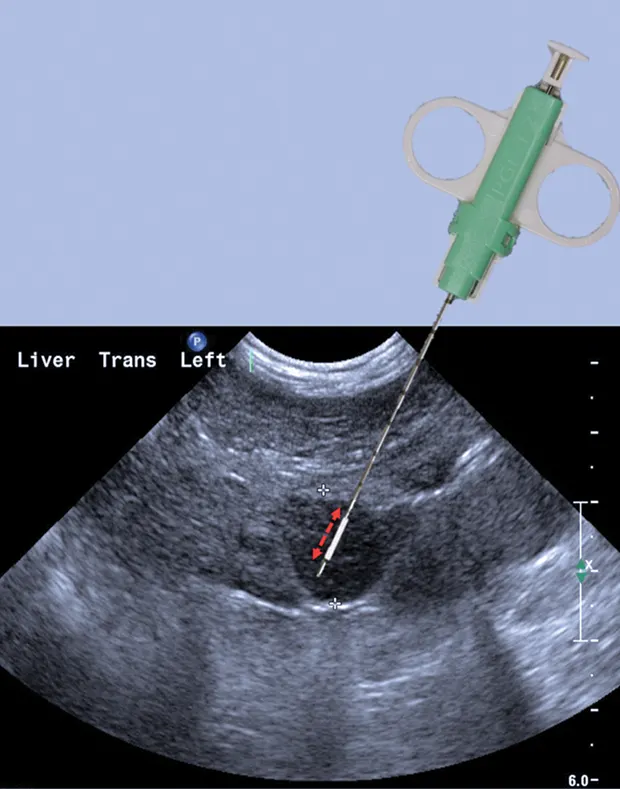

Larger-gauge biopsy devices (14-gauge) increase the risk for hemorrhage, especially with passage of the needle deep into the liver. However, a major limitation of needle biopsies is the size of the sample retrieved, so a balance between patient safety and sample size needs to be considered.4,5 Biopsy needles vary in actual length and in length of the biopsy stylet for the core liver tissue to be obtained (typically 12, 15, or 20 mm long). Semiautomated devices tend to have a fixed stylet length, whereas biopsy length can be altered with some of the fully automated devices. The fully automated biopsy device (Figure 3A; see Image Gallery) advances into the tissue a set distance depending on the length of the inner stylet that receives the tissue. This distance should be taken into account before firing the device to ensure that a proper specimen is likely to be collected and that non-target tissues are not sampled. For the semiautomated biopsy device, the inner (receiving) stylet is manually advanced prior to firing the outer cutting portion of the biopsy device (Figure 3B; see Image Gallery). On average, 3 to 4 quality samples are taken and placed in formalin for routine histopathology. Other types of sample handling will be required for determining copper content or specific types of tissue testing, as well as for culture and susceptibility testing. The clinician should be prepared ahead of time for the type of fixation or sample handling procedures so that the tissue sample is fresh and handled in an appropriate fashion.

Biopsy needle tract within the patient after firing and just before removing the biopsy device (B). Post-biopsy hemorrhage often collects between hepatic lobes as seen in this image (white arrow heads) (C). The echogenic fluid represents acute hemorrhage. Color flow Doppler post-biopsy ensures there is no persistent hemorrhage in the peritoneal space (D). Power Doppler imaging is the most sensitive form of Doppler to detect the presence or absence of blood flow.

Step 6: Sample the Lesion

When using a semiautomated device in the correct position, the inner stylet can be advanced through the desired biopsy location and when ready, the cutting outer cannula can be deployed. If the stylet is a 20-mm cutting length, advance the inner stylet at least another 2.5 cm deep in the tissue. Always be mindful of the depth of the tip of the needle. Ultrasound calipers can be used to determine the depth the device tip will travel. With a fully automated device, the needle tip is advanced to a location that is 1.2 to 2 cm from the area of interest, which is in the trajectory of the device. Remember that when fired, the inner stylet advances and the outer cutting cannula fires in rapid succession (microseconds). Where exactly the tip will end up depends on many factors, including hand steadiness. Again, when triggered, both the inner stylet and cutting cannula will advance through the lesion. Whichever device is deployed, once fired, the needle should be held steady for several seconds to evaluate for any immediate hemorrhage or areas of linear hypoechogenicity. Remove the device and hand to an assistant for removal of the core liver sample.